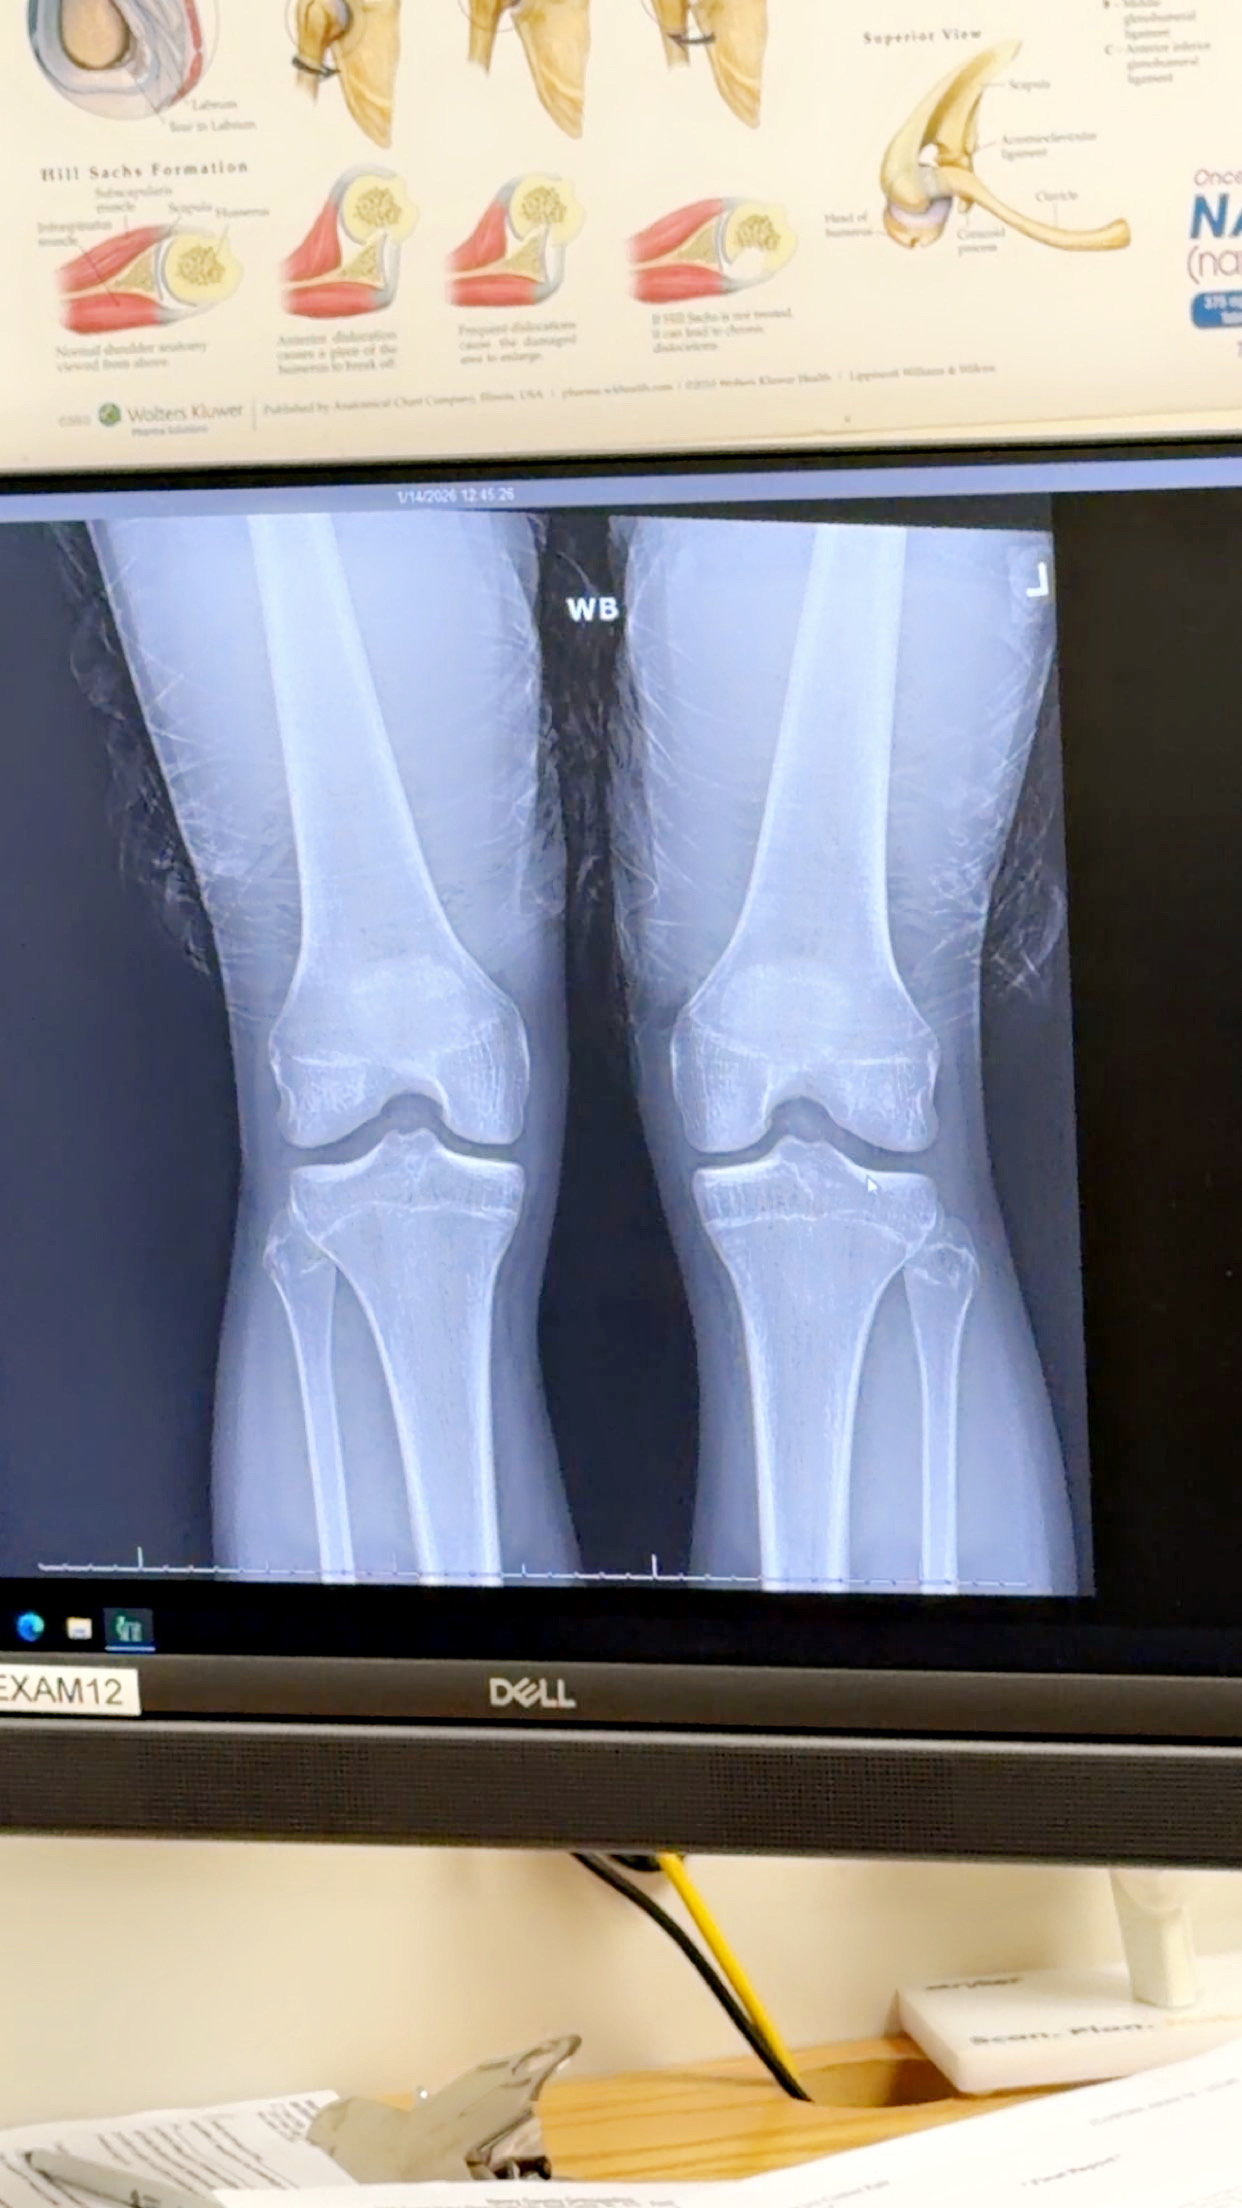

I was wondering if my growth plates are still open or closed and if so how long do you possibly think ?? The doctor was a idiot and couldn’t read them.

def more than 90% fused

your growth plates are still SLIGHTLY open, i doubt they will be open for much longer.

Thanks appreciate it I’m 16 turning 17 in April should I get on aromatase inhibitor ?